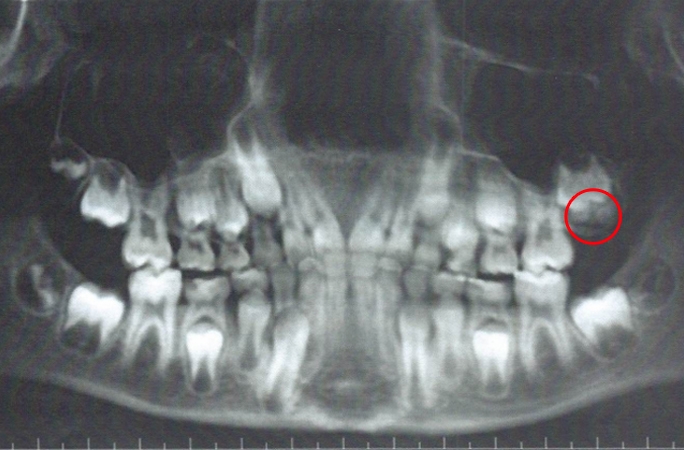

醫生發現智慧齒蹤跡

去年4月,Ryan到診所進行牙齒矯正檢查,主治醫生Kelly博士通過X光片驚訝發現,Ryan的左上排長出了智慧齒,更與臼齒疊在一起。一般而言,人們會在17至25歲才長出智慧齒,也是最後才生長出的第三大臼齒。Ryan的情況無疑是需要提早剝掉智慧齒,才能讓臼齒有生長空間。對此他也感到震驚,並表示自己根本對智慧齒的存在毫無感覺。